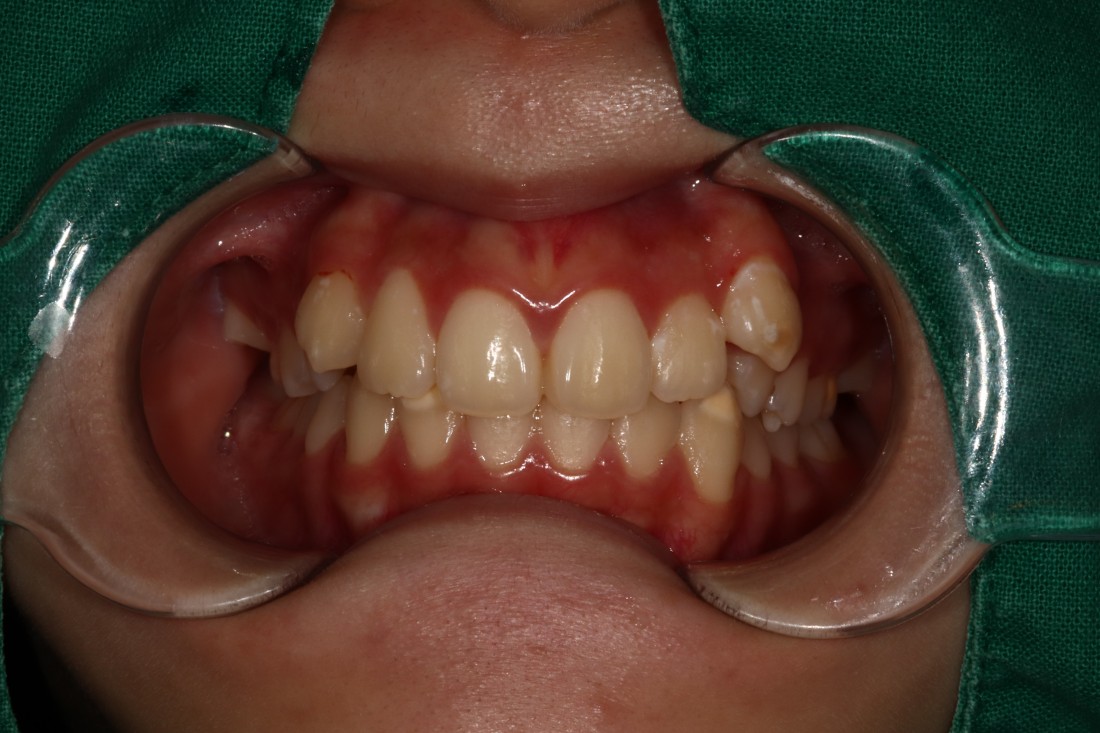

덧니는 과거에는 귀여운 이미지를 줘서

선호하기도 하였지만,

요즘은 고른 치열을 만들어서

세련된 외모를 완성하는 것이

필수 트렌드가 되고 있습니다.

광주 교정치과에서는

3차원 105항목 정밀검사를 통해

발치교정 / 비발치교정 을 포함하여

정확한 치료계획을 세우고 있습니다.